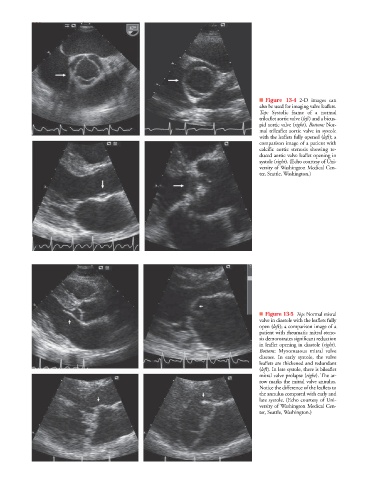

■ Figure 13-4 2-D images can

also be used for imaging valve leaflets.

Top: Systolic frame of a normal

trileaflet aortic valve (left) and a bicus-

pid aortic valve (right). Bottom: Nor-

mal trileaflet aortic valve in systole

with the leaflets fully opened (left); a

comparison image of a patient with

calcific aortic stenosis showing re-

duced aortic valve leaflet opening in

systole (right). (Echo courtesy of Uni-

versity of Washington Medical Cen-

ter, Seattle, Washington.)

■ Figure 13-5 Top: Normal mitral

valve in diastole with the leaflets fully

open (left); a comparison image of a

patient with rheumatic mitral steno-

sis demonstrates significant reduction

in leaflet opening in diastole (right).

Bottom: Myxomatous mitral valve

disease. In early systole, the valve

leaflets are thickened and redundant

(left). In late systole, there is bileaflet

mitral valve prolapse (right). The ar-

row marks the mitral valve annulus.

Notice the difference of the leaflets to

the annulus compared with early and

late systole. (Echo courtesy of Uni-